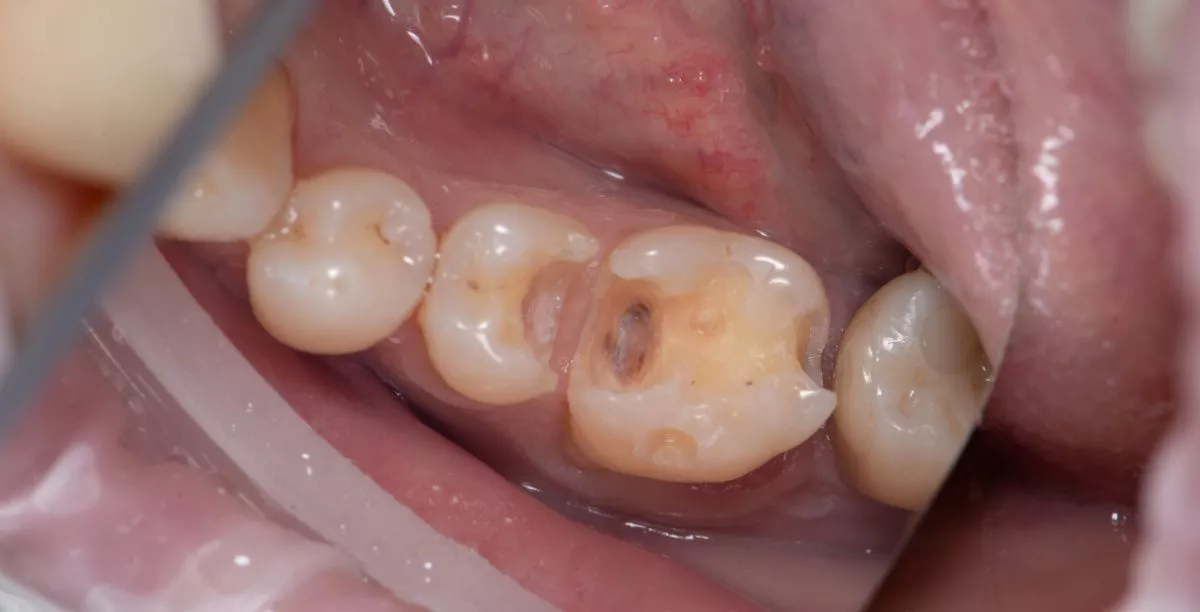

Лечение скрытого кариеса под старой пломбой

Лучшие стоматологические клиники. Лечение скрытого кариеса под старой пломбой  - до процедуры